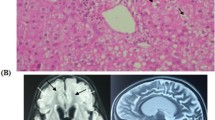

Family pedigree analysis, brain MRI images and variant analysis of IARS2. A. Pedigree analysis of patient 1 and patient 2 from two unrelated Chinese families. Rectangles indicated males, circles female, solid circle rectangled the affected individuals and probands were pointed out by arrows. B. Brain MRI images of patient 1 and 2. The patient 1 on the left showed lesions in the thalamus, periaqueductal, cerebellum and pons when he was 4 years old. The arrow pointed to the high signal were diseased areas. The patient 2 on the right showed long T1 and T2 signals in the lateral caudate nucleus and putamen, reduced cerebral white matter, bilateral basal ganglia symmetry damage, and cerebral dysplasia. The circled pointed to the symmetrical patchy were diseased areas. C. Sequencing chromatograms of IARS2 in patients and their parents. The arrows indicated the mutation sites. D. Quantitative analysis results of IARS2 in patient 2 and his parents

Patient 2, a 4-year-old boy, was born in a Chinese family with healthy parents (Fig. 1A). He was G3P3 with an abdominal delivery, and weighed 4350 g at birth. The child was admitted to the hospital at one and a half years old, weighing 13 kg, with a head circumference of 46 cm and a height of 73 cm. He couldn’t speak and had been diagnosed with growth retardation. It was hard for him to sit stably, and he was unable to walk or eat alone. The patient was readmitted at age 3 and diagnosed with dystonia and neurodevelopmental delays. Laboratory examination showed increased blood lactate (6.24 mM, normal range 0.50–2.20 mM), β-hydroxybutyric acid (1.05 mM, normal range 0.02–0.27 mM), and creatine kinase (1854.59 U/L, normal range 50–319 U/L). Brain magnetic resonance imaging (MRI) revealed long T1 and T2 signals in the lateral caudate nucleus and putamen, reduced cerebral white matter, bilateral basal ganglia symmetry damage, and cerebral dysplasia (Fig. 1B). He was subsequently diagnosed with LS. After filtering with established criteria, WES and mitochondrial genomic sequencing did not detect potential disease-causing gene mutations. Subsequently, whole genome sequencing (WGS) was performed. Following filtering with established criteria, a novel site variant (c.2450G > A) and a deletion variant with 1 and 2 exons (c.1_390del, NC_000001.11: g.220267444_220269568del) in the IARS2 gene were found, and no clinically significant mitochondrial genomic-related variants were observed. Segregation analysis confirmed that c.2450G > A was from the patient’s mother and c.1_390del was from the patient’s father (Fig. 1C). As shown in Fig. 1D, heterozygous mutations in IARS2 exon 1 and 2 of the patient were found by CNV-Seq. Quantitative PCR results showed that the mRNA level of IARS2 exon 1 and 2 in the patient and his father were significantly decreased compared with both age-matched controls and the patient’s mother.